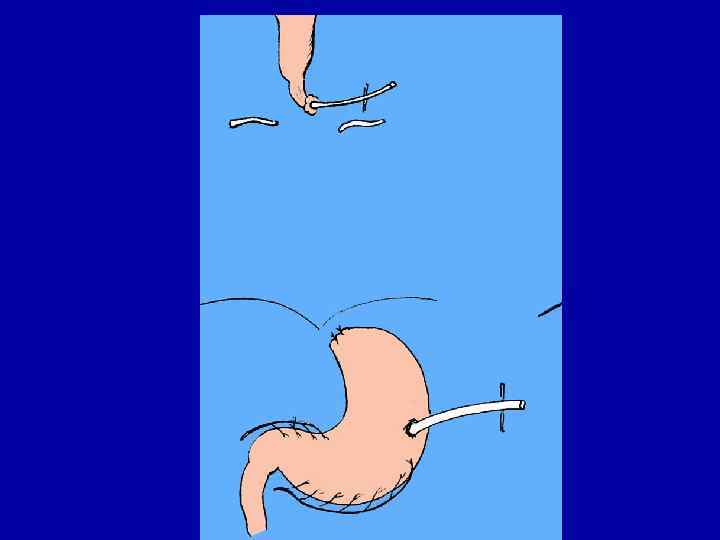

Схема пластики пищевода желудочной трубкой